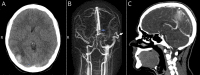

Cerebral Venous Sinus Thrombosis in a Pediatric Patient With COVID-19